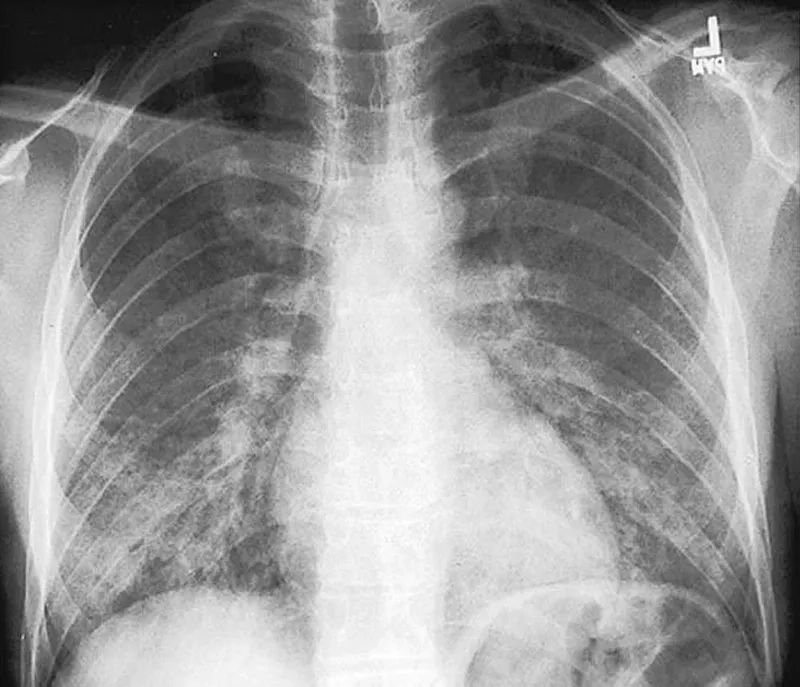

• A diagnosis of PCP often involves a chest x-ray, which typically shows diffuse bilateral infiltrates, a key indicator for healthcare providers.

Image of the disease Pneumocystis Pneumonia